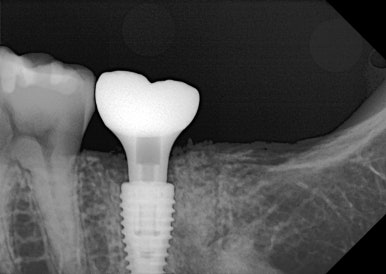

🦷 사용 임플란트: 메가젠 블루다이아몬드

이번 케이스에서는

👉 메가젠 블루다이아몬드 임플란트를 사용했습니다.

✔ 높은 강도

✔ 빠른 골유착

✔ 어금니처럼 힘 많이 받는 부위에 적합

👉 특히 저작력이 강한 부위에서

안정성이 뛰어난 제품입니다.